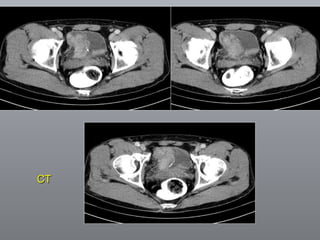

Câncer de Bexiga Estudos de imagens Diagnóstico Ultrassonografia Urografia excretora Estadiamento CT RNM Rx tórax  Cistoscopia + biópsia + biópsias randomizadas

CT